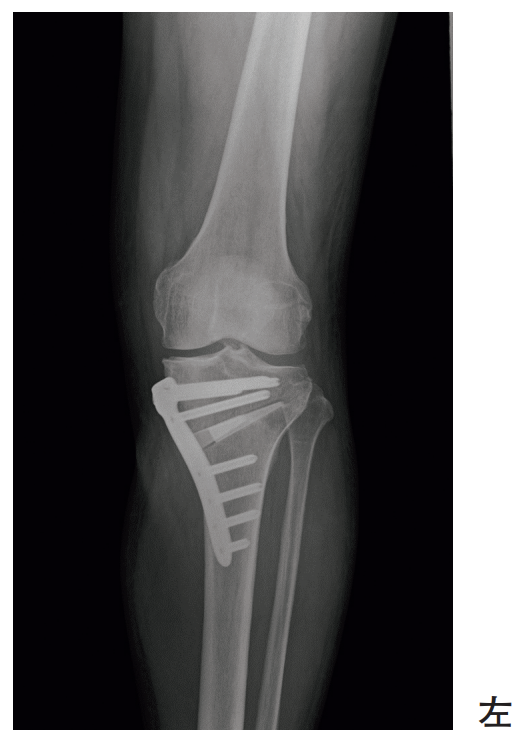

60歳の男性。内側型の変形性膝関節症に対して手術療法が行われた。術後のエックス線写真を別に示す。

骨癒合を促進させるために最も優先度が高い治療法はどれか。